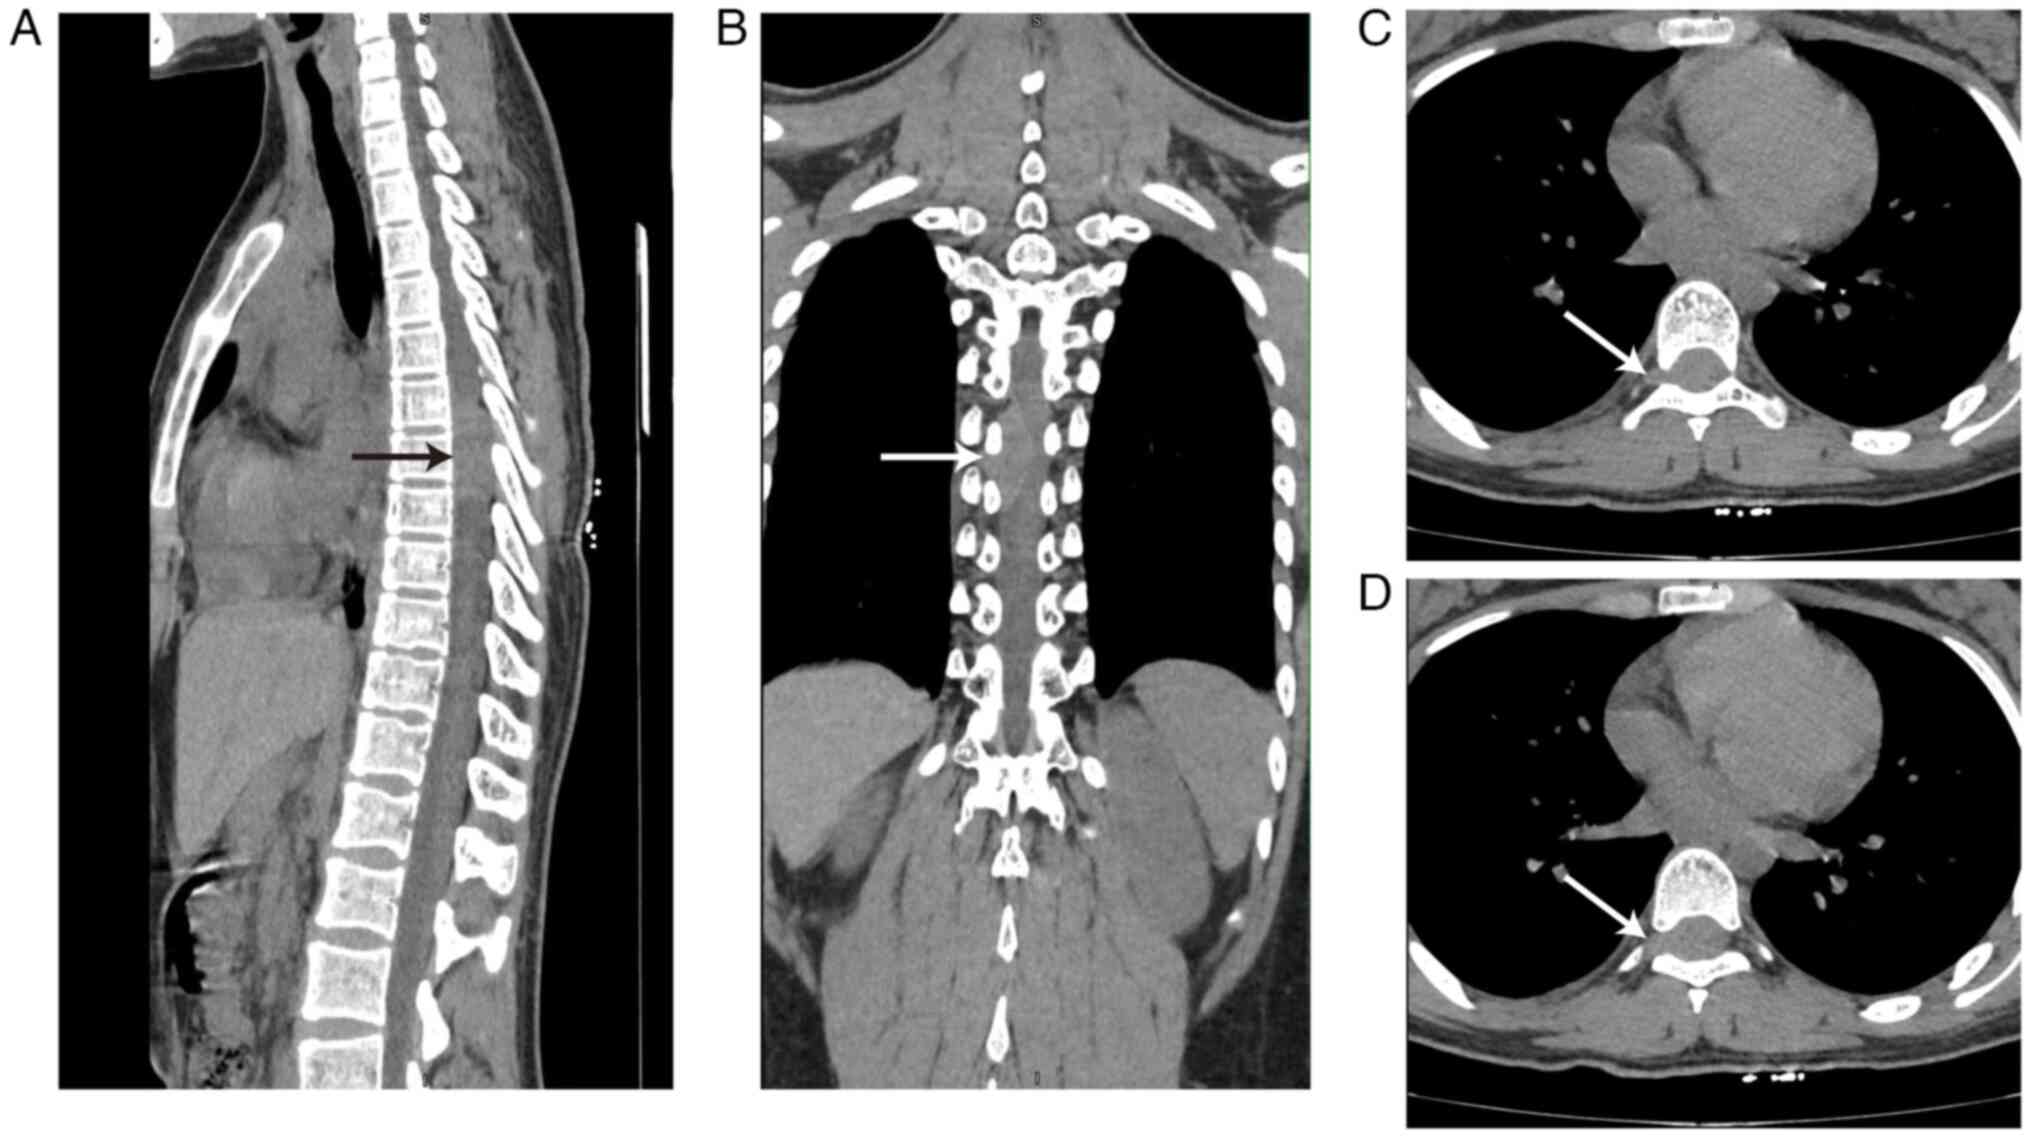

The following descriptions of the imaging examinations were based on reports by 2 or 3 independent radiologists. Magnetic resonance imaging (MRI) examination demonstrated an oval mass (~1.7×2.1×4.0 cm3; front-back × left-right × up-down) in the extraspinal subdural space and the right side of the intervertebral foramen in the T6-8 spinal canal. The mass exhibited high signal intensity on T2-weighted images and isointensity on T1-weighted images. The signal intensity demonstrated uneven enhancement in the lesion after contrast enhancement. At the same level, spinal stenosis and intervertebral foramen enlargement were observed and the spinal cord appeared significantly compressed and displaced to the left side (Fig. 1). An MRI diagnosis of neurogenic tumor was considered. Non-contrast CT imaging demonstrated a mass ~1.5×2.3×3.4 cm3 in the T6-8 plane with intervertebral foramen enlargement and the spinal cord appeared significantly compressed and displaced to the left side (Fig. 2). Neurogenic tumors were considered based on CT examination. No obvious abnormalities were demonstrated upon hematological examination of the patient.

Figure 2.

Non-contrast CT images of a mass in the T6-8 plane (arrows). (A) Median sagittal section demonstrated aggressive and invasive growth and indistinct borders from surrounding tissues. (B) Coronal section demonstrated that the spinal cord was significantly compressed and displaced to the left side. (C) Transverse sections demonstrated that the tumor grew out of the spinal canal through the intervertebral foramen. (D) Transverse sections demonstrated that the tumor grew out of the spinal canal through the intervertebral foramen significantly.